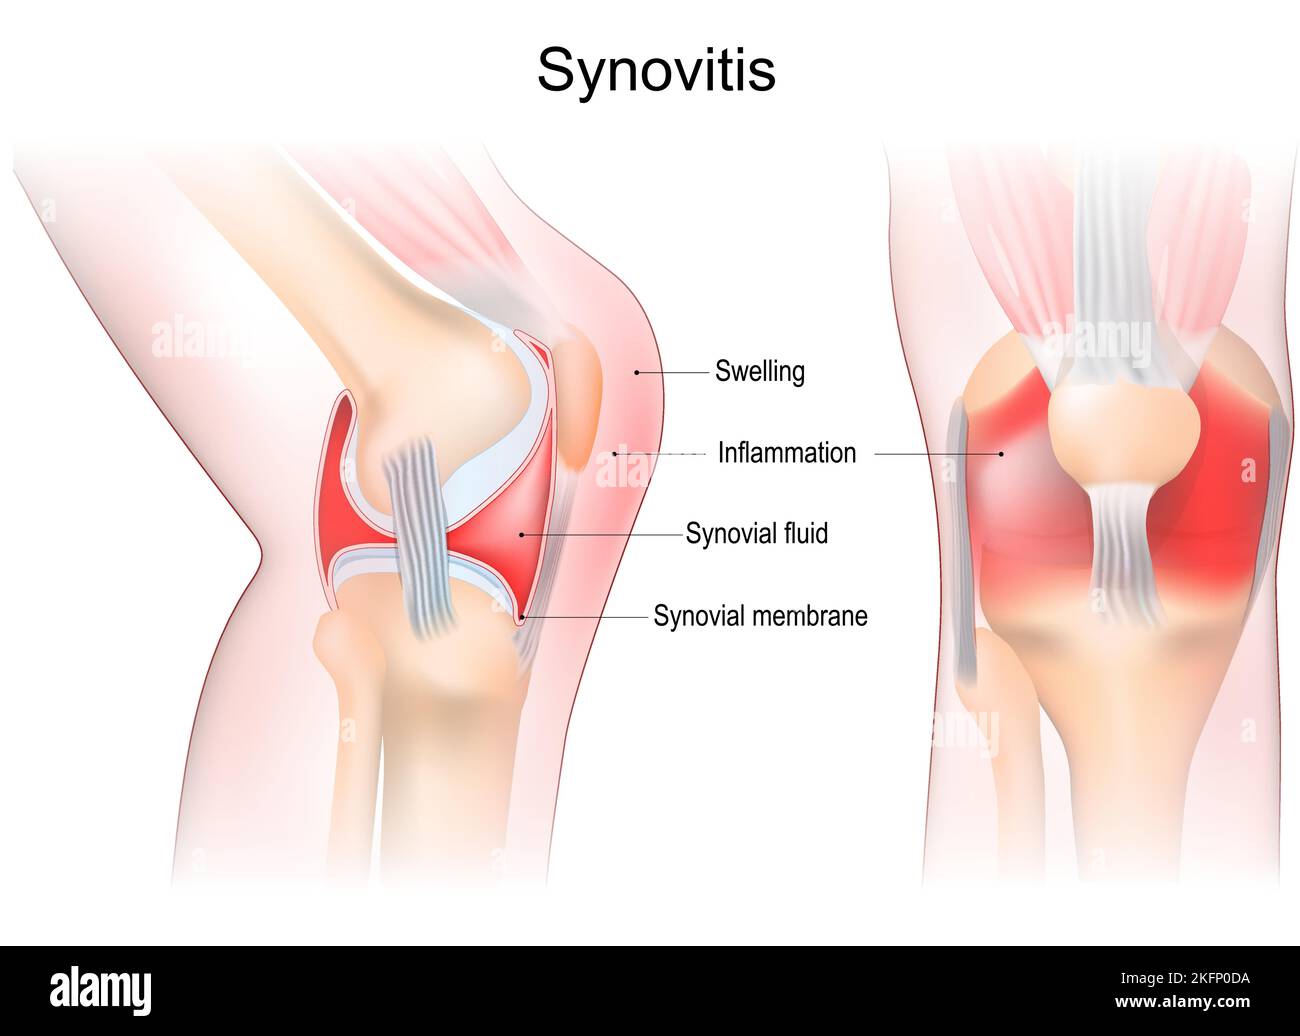

synovitis of a Knee. Close-up of joint with inflammation of the synovial membrane. Signs and symptoms of the disease. Synovial joint anatomy. Stock Vectorhttps://www.alamy.com/image-license-details/?v=1https://www.alamy.com/synovitis-of-a-knee-close-up-of-joint-with-inflammation-of-the-synovial-membrane-signs-and-symptoms-of-the-disease-synovial-joint-anatomy-image491593462.html

synovitis of a Knee. Close-up of joint with inflammation of the synovial membrane. Signs and symptoms of the disease. Synovial joint anatomy. Stock Vectorhttps://www.alamy.com/image-license-details/?v=1https://www.alamy.com/synovitis-of-a-knee-close-up-of-joint-with-inflammation-of-the-synovial-membrane-signs-and-symptoms-of-the-disease-synovial-joint-anatomy-image491593462.htmlRF2KFP0DA–synovitis of a Knee. Close-up of joint with inflammation of the synovial membrane. Signs and symptoms of the disease. Synovial joint anatomy.